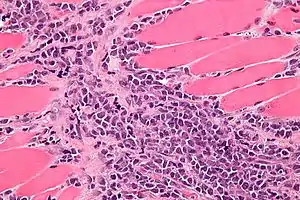

| Micrograph of a myeloid sarcoma within muscle. H&E stain. | |